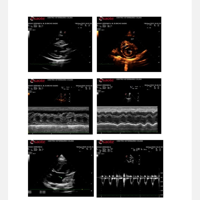

Fizemos uma série de exames com cardiologistas e descobrimos a existência de um tumor no coração do Noah, tumor este que, até agora, ainda não conseguimos descobrir se é malígno ou benigno. Este tumor, quando inflamado, acaba gerando e acumulando líquido no pericárdio, ao redor do coração do Noah, e isso faz com que o coraçãozinho dele fique apertado, funcionando com dificuldade. O coração, por estar em sofrimento, acaba não conseguindo bombear sangue o suficiente para o restante do corpo, fazendo com que os órgãos fiquem sobrecarregados e que mais líquido se acumule, se espalhando também para a região abdominal. Mesmo já tendo feito cerca de quatro drenagens (sendo três no coração e uma no pulmão, que também já acumulou líquido), este problema fica indo e vindo, nos deixando desamparadas. Ele, quando está com líquido retido, não consegue deitar direito para dormir, fica dormindo sentado, perde o apetite, fica com a respiração pesada…

Já fizemos rifas e contamos com doações nas redes sociais, mas as nossas idas ao veterinário tem sido semanais, às vezes mais de duas vezes por semana, e o dinheiro tem sido uma grande questão. Agora, o próximo passo é fazer uma tomografia para descobrirmos sobre o tumor que, sendo benigno, o Noah poderá passar por uma cirurgia para a retirada do pericárdio, que vai impedir que esse líquido volte a se acumular, podendo dar a ele uma vida normal.